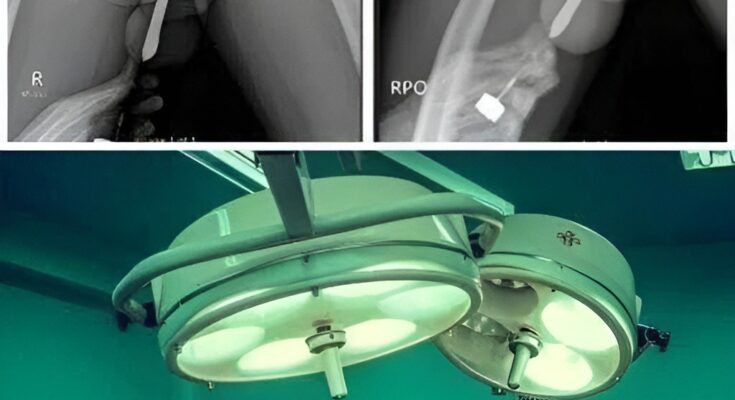

The object caused severe internal injury, leading to pain, bleeding, and the risk of infection. She was taken to the hospital, where doctors performed emergency treatment to remove the object and prevent further complications.

Medical staff were able to stabilize her, but experts said the outcome could have been much worse without urgent care. Serious injuries like this can lead to lasting damage or dangerous infection if not treated quickly.